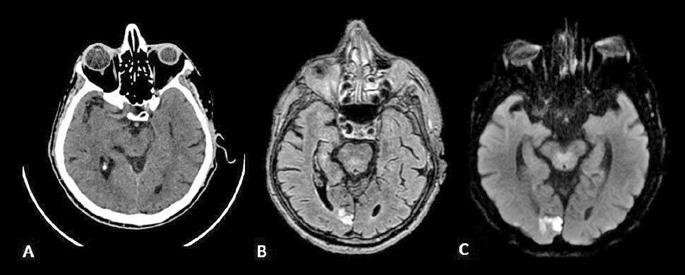

Figura 1. Pacient de 57ani cu simptomatologie acută sugestivă pentru AVC ischemic acut: CT -ul nativ nu a decelat elemente de semiologie sugestive pentru AVC ischemic acut (A), însă secvențele IRM au evidențiat o arie în hipersemnal FLAIR (B) și cu restricție de difuzie (C) localizată occipital paramedian dreapta, sugestivă pentru AVC ischemic acut (Spitalul Clinic de Urgență „Prof. N. Oblu“, Iași)

În contrast, imagistica prin rezonanță magnetică, în special secvențele de difuzie, oferă o sensibilitate superioară pentru detectarea precoce a infarctului ischemic,

fiind capabilă să identifice modificări la nivel celular la doar câteva minute după debutul simptomelor (Figura 1) (Mouridsen et al., 2020), (Nukovic et al., 2023). De asemenea, IRM este capabilă să ofere o evaluare superioară a integrității parenchimului cerebral, a viabilității țesutului și a extinderii leziunii ischemice, facilitând o caracterizare mai detaliată a AVC-ului ischemic (Cortés-Albornoz et al., 2025).